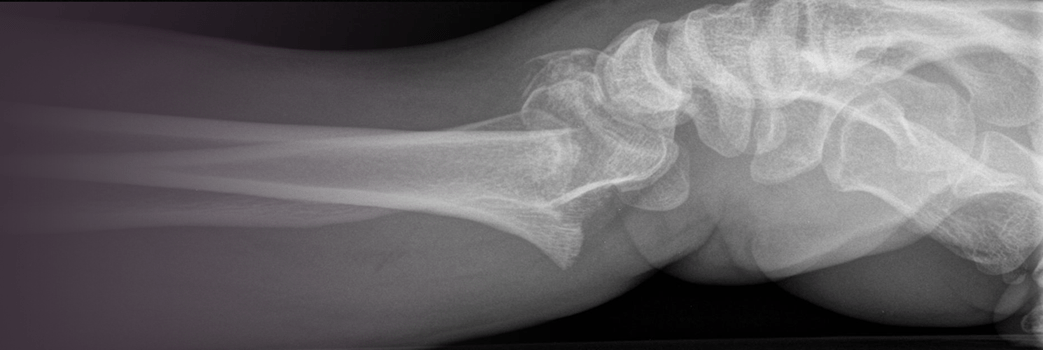

Wrist and forearm fractures

Fractures and dislocations of the elbow